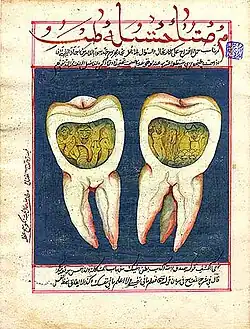

Im arabischsprachigen Raum glaubte man unter Rückgriff auf ältere Traditionen an Zahnwürmer. Dies zeigt das Werk des Muhammad ibn Zakarīyā ar-Rāzī, der das Verhältnis von Leib und Seele als von der Seele bestimmt ansah, ebenso wie die Werke Avicennas oder von Abulcasis. ʽUmar ad-Dimašqi, der um 1200 in Damaskus lehrte, lehnte hingegen in seinem Buch des Auserlesenen über die Enthüllung der Geheimnisse und das Zerreißen der Schleier den Zahnwurm ab, vor allem die Scharlatanerie, die mit Würmern getrieben wurde.[22]

Abu l-Qasim (936–1013), im Westen als Abulcasis bekannt, bezeugt in seiner 30-bändigen medizinischen Schrift Kitāb at-Taṣrīf (arabisch كتاب التصريف) sein umfassendes Wissen und Können in der Chirurgie der Zähne, der Zahnstabilisierung mit Gold- und Silberdraht und bei der Behandlung von Zahnfleischproblemen, einschließlich der Zahnprophylaxe. Abulcasis perfektionierte viele zahnärztliche Instrumente, wie man seinen Skizzen entnehmen kann.